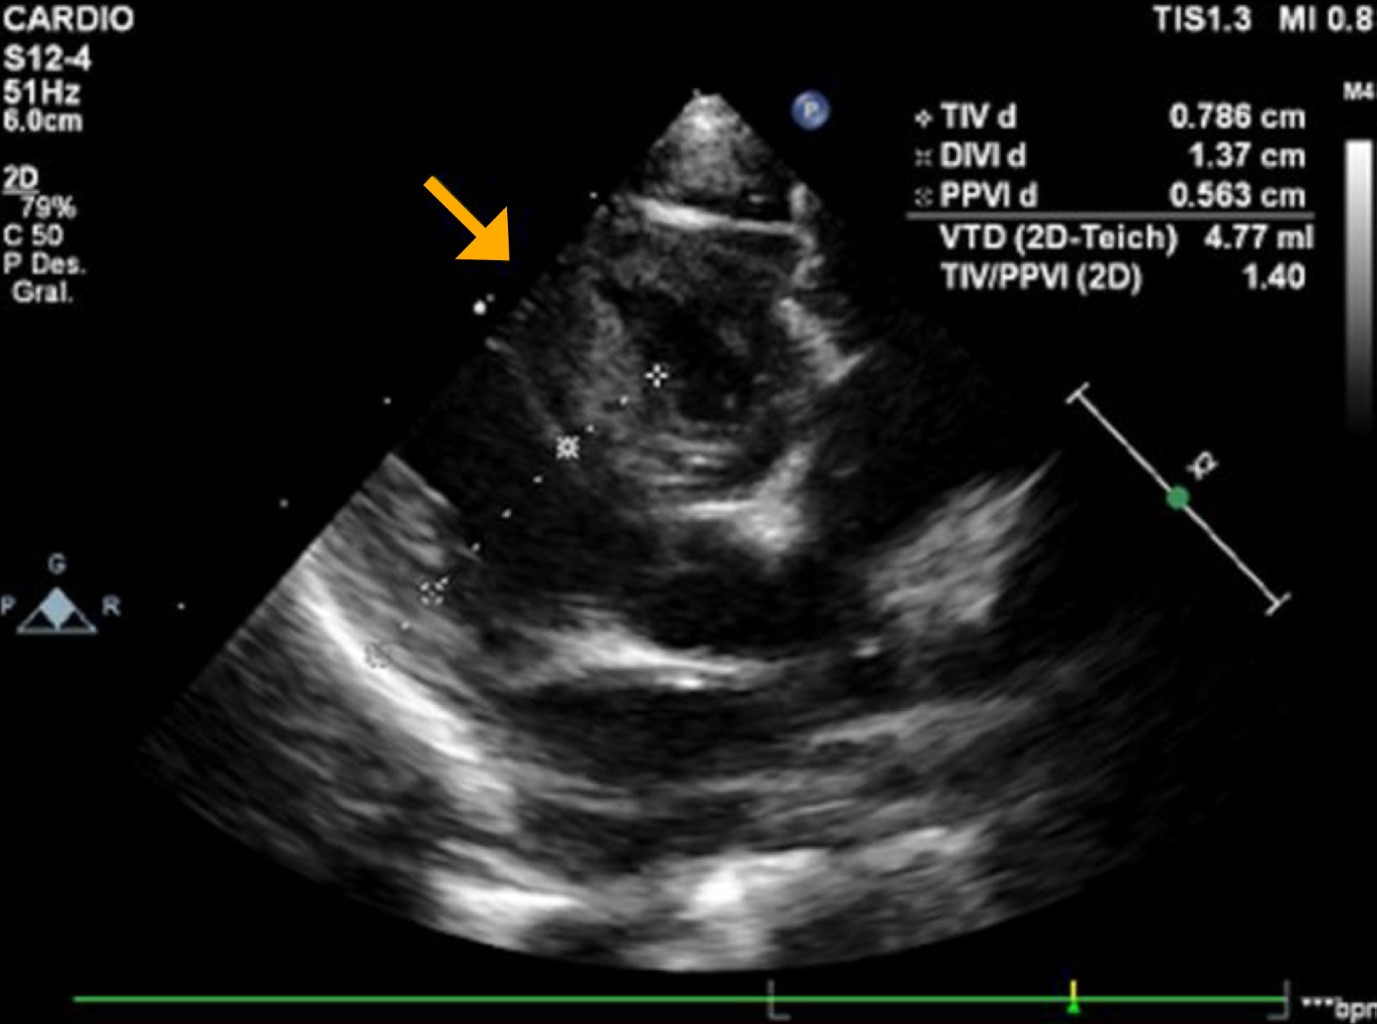

Ante datos sugestivos de miocardiopatía se realizó ecocardiograma transtorácico, que mostró aumento de grosor miocárdico en ventrículo izquierdo, de predominio septal que se consideró grave (tabique interventricular 7.8 mm, z-score +4 para peso y talla). No se evidenciaron datos de obstrucción intraventricular, mientras que la función y contractilidad ventricular estaban conservadas. Se diagnosticó miocardiopatía hipertrófica asimétrica septal no obstructiva (Figuras 3 y 4).

Figura 4